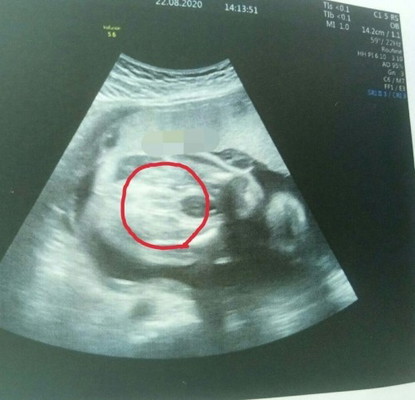

สอบถามอีกแล้วจ้าาา. รอบนี้ตกลงหญิงหรือชายค่ะแม่ๆ หมอบอกไม่แน่ใจมา2-3รอบแล้ว อิแม่ต้องลุ้นทุกเดือน